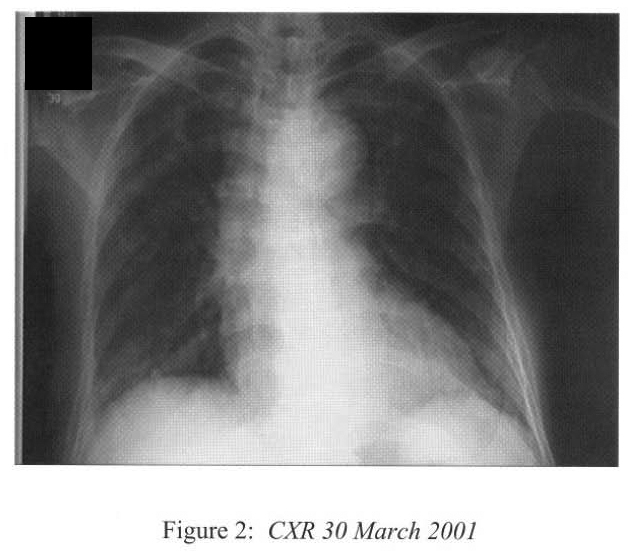

One day later she became hypotensive. There has been no change in her steroid doses and she remained afebrile. Peritoneal dialysis was withheld and intravenous fluid replaced. She passed tarry stool and this was supported with transfusion. The hypotension persisted and she eventually required inotropes infusion (dopamine and dobutamine) for blood pressure support. Her general state deteriorated with lethargy, vomiting and anorexia. She was further supported with parenteral nutritional. Dyspnoea recurred during this period of time. CXR showed diffuse bronchopneumonia in addition to the persistent right lower zone consolidation. (Figure 2) The creatinine level rose up to 912 umol/L.

Radiological features are also diverse and variable 15,16.On the chest radiograph, early signs include miliary shadows, diffuse reticular interstitial opacities, patchy alveolar opacities, segmental or lobar opacities. In the advanced stage, there can be extensive airspace shadows affecting both lungs, with occasional pleural or pericardial effusion. Without treatment, ARDS quickly evolves. Rarely, ARDS develops after antihelminthic treatment due to release of toxic breakdown products 17.On the abdominal radiograph, there can be thickened mucosal folds, segmental small bowel dilatation or perforation. Among all these variable radiological features, a characteristic pattern of Strongyloides hyperinfection has been described by the radiologists of Hong Kong, which consist of fleeting and rapidly changing CXR signs, predominant small bowel abnormality on AXR, and close temporal relationship of CXR & AXR signsl8. Detection of larvae in stool or other specimens is difficult (Table 1). Serological diagnosis19 is an attractive alternative but it is not available in Hong Kong.